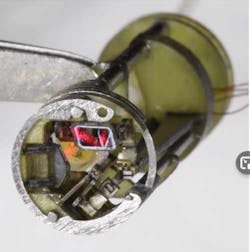

The device, which is just 6 mm in diameter and 16 mm in length, contains two mirrors controlled by piezoelectric actuators that direct the laser’s position (Fig. 2) in a complex opto-electromechanical device. It’s possible to integrate the device with existing surgical tools to control the position of a fiber-delivered laser.

To ensure that an adequate range of motion can be developed within such a small device, the team used miniature, compliant mechanisms to convert the linear motion of the actuators into the rotational motion of integrated mirrors. Further, to focus and position the laser beam, the compact “teleoperated” device uses two independent, orthogonal mirrors driven by piezoelectric bending actuators to rotate with the help of flexure-based linkages, and off-the-shelf optical components to focus a fiber-coupled laser beam (Fig. 3).